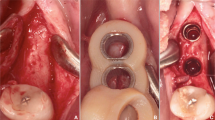

For virtual planning, lateral cephalograms (Orthophos SL 2D, Dentsply Sirona, York, Pennsylvania, USA; 73 kV, 15 mAs, effective radiation 9.2 s) were taken. Therefore, the heads were aligned with optical localizers to the midsagittal plane and Frankfurt horizontal plane to ensure symmetry. Cast models were prepared based on impressions using Impregum Penta (3M ESPE, Neuss, Germany), according to the manufacturer’s instructions. This called for automatic mixing in the corresponding Pentamix device and taking the impression material into the oral cavity for 7 min to ensure complete setting. All impressions were previously produced with super-hard plaster (Alpenrock, Amann Girrbach, Koblach, Austria) rotated in a vacuum mixer. To ensure that final hardness had been reached, the models were digitally transferred after 24 h using a 3D model scanner (orthoX scan, Dentaurum, Ispringen, Germany) that provided an average accuracy scanning of 0.5 mm [13]. Lateral cephalograms and corresponding models were matched by software support (TAD match, OnyxCeph, Image Instruments GmbH, Chemnitz, Germany) and used for planning of the appropriate position, as previously described [12]. The templates were produced on the working model that was manufactured by a 3D printer (Form 2, Formlabs, Somerville, MA, USA). The heads were randomly allocated into either tooth- or gingiva-borne groups. Finally, fully guided templates were manufactured with a two-component silicone (Transpasil, Kaniedenta GmbH & Co. KG, Herford, Germany) (Fig. 1a, b). The templates were incorporated into the maxilla, and the precise fit was visually and manually controlled before and during surgery. In all cases, implantation was performed by one experienced surgeon with one assistant taking care of the template position. Placement was performed without predrilling using a contra-angle handpiece drive (Prosthodontic implant driver, W&H, Bürmoos, Austria) with a speed of 25 rpm and an adjustable torque control with a maximum of 40 Ncm. The insertion stopped automatically after the mini-implant reached the final depth by separation of the implant from the insertion aid.

Postoperative CBCT scans (Galileos, Sirona, Bensheim, Germany; 98 kV, 25 mAs, effective radiation time 5 s, FOV: diameter 215 mm, voxel size 160 μm) were performed after the heads were aligned with optical localizers to the midsagittal plane and Frankfurt horizontal plane to ensure symmetry. Then, the scans were transformed into the Digital Imaging and Communications in Medicine (DICOM) format and imported with the virtual cast models into the coDiagnostiXTM software (version 9, Dental Wings GmbH, Freiburg, Germany). The outcome assessment was blinded. In all cases, the maximum possible superposition was adjusted using the automatic software function. For this purpose, the cast model was matched to at least three clearly visible matching references distributed over the arch (Fig. 2). The vestibular tooth surfaces including occlusal surfaces of the first molars as well as the distoincisal angle of the left/right central incisors were defined as references. Three-dimensional measurements (coronal, sagittal, and axial planes) included the distances between the matched files of the implant axis, implant tip and centre of the implant shoulder (Fig. 3a). Between the planned and postoperative vertical implant positions, the distances between the anterior and posterior implant shoulders and the contact of the gingiva at the implant in the sagittal planes were evaluated (Fig. 3b).